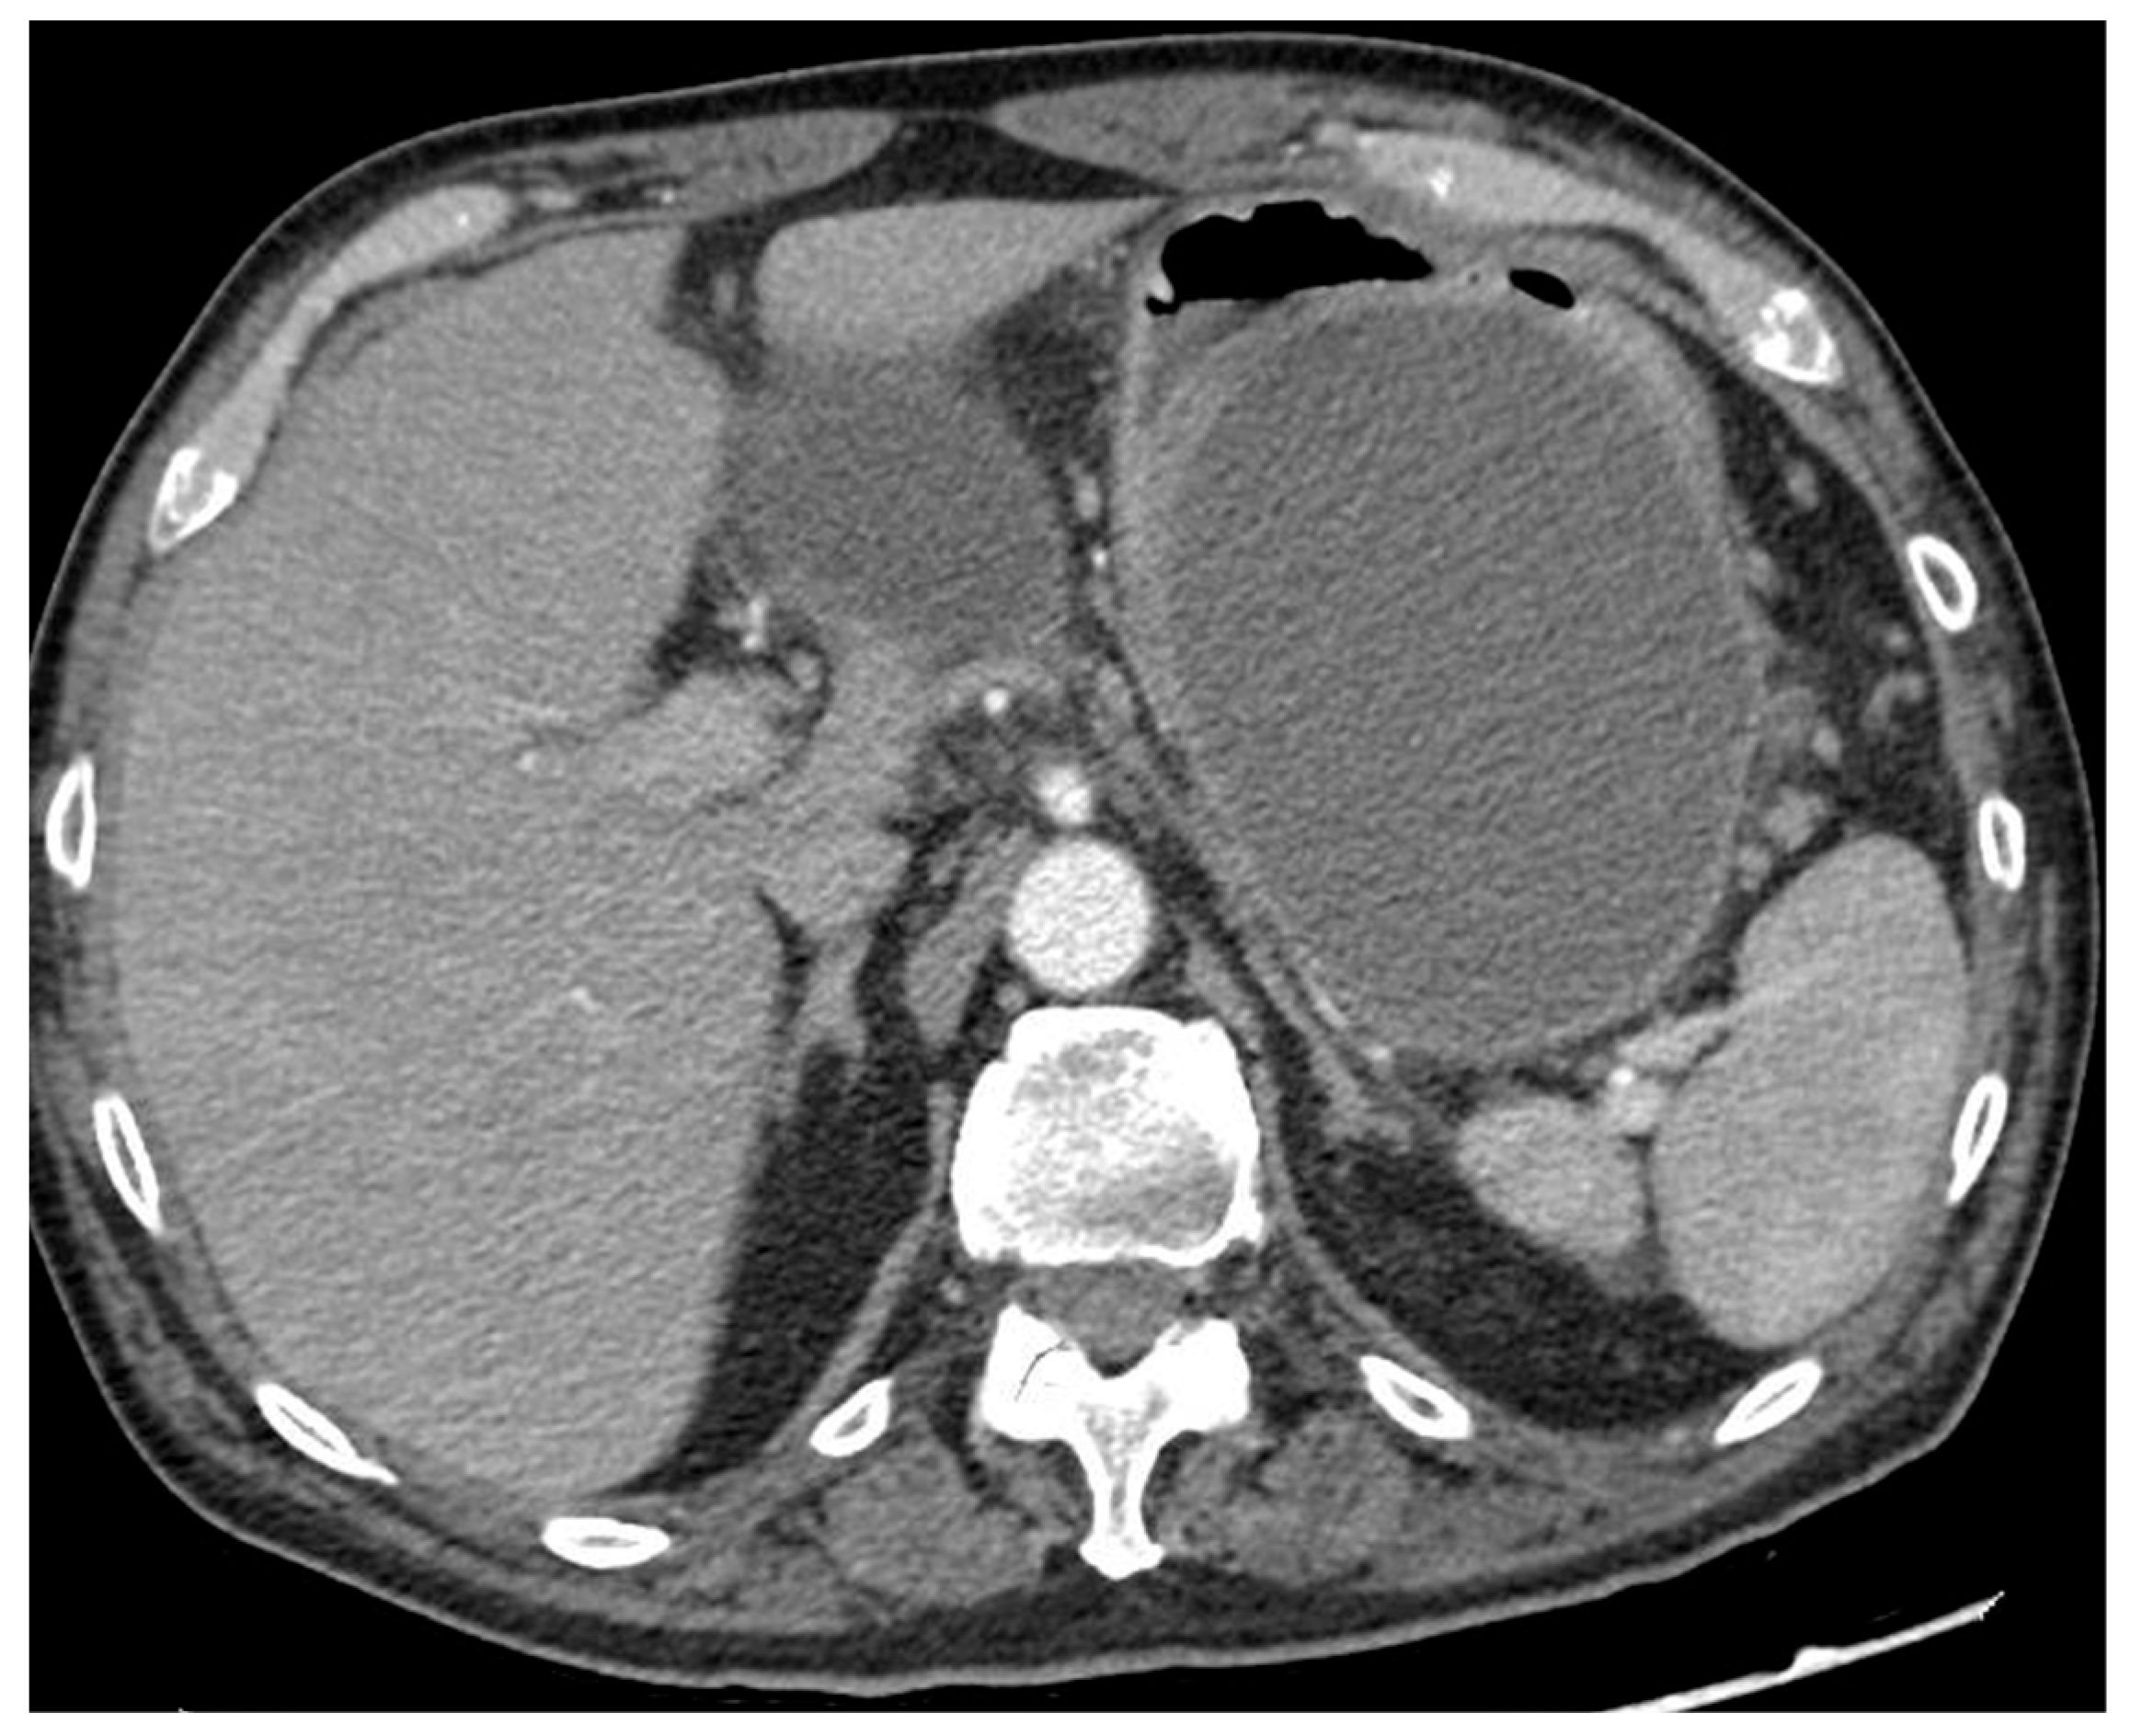

Figure 2.

CT scan image of a large collection determining symptomatic gastric compression. CT, computed tomography.